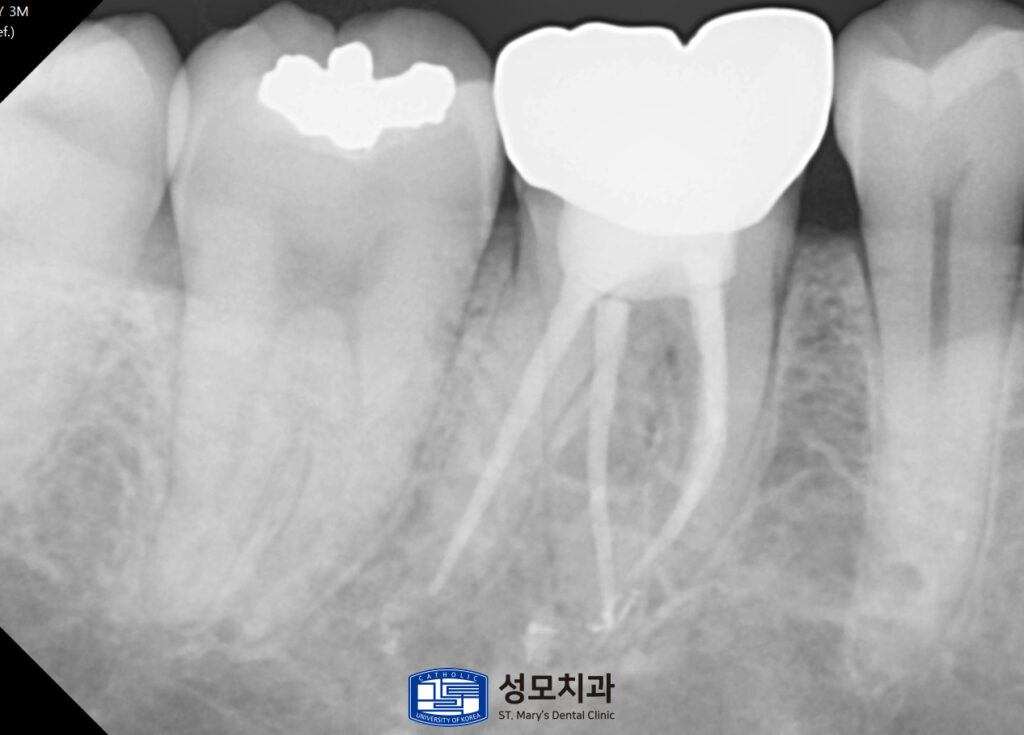

아말감 수복 치아는 기존 수복물을 제거해

균열과 2차 우식의 범위를 눈으로 확인한 뒤

치질을 보존하면서 모두 제거했습니다.

근관 내 소독과 세척을 통해 염증을 정리하고

레진 코어로 제거했던 부위를 보강했습니다.

이후 맞춤 형상의 크라운으로 전체를 감싸

씹는 힘이 특정 벽에 집중되지

않도록 씌워주었습니다.